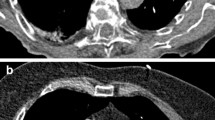

Objective image quality

Key findings for objective image quality are shown in Table 2, with corresponding p-values listed in Table 3. Enhancement in the pulmonary arterial tract and aortic tract was lowest in protocol D, where the least CM was administered, and highest in protocol A, where the most CM was injected. However, there were no significant differences in average pulmonary arterial attenuation between the two high-flow protocols (A and B with 5 ml/s), and between the two protocols with intermediate contrast volume (B and C with 50 ml). Protocol D showed significantly lower SNR and CNR-values in the pulmonary arterial tract compared to all other protocols, while no significant differences were observed between protocols A, B and C concerning pulmonary arterial SNR or CNR. For the aortic tract, there was no significant difference in attenuation and SNR between protocols A and B, while aortic enhancement and SNR decreased significantly with lower flow or lower CM volume in protocols C and D. Aortic tract CNR was significantly lower for protocol D compared to all other protocols, whereas protocols A, B and C showed no significant differences. Venous tract attenuation was highest for protocol D, and lowest for protocol B, with intermediate values in protocols A and C. Figure 2 demonstrates exemplary CTPA and iodine map images for each protocol.

Subjective quality of iodine maps for protocol D (median 2 for all resolutions) was rated significantly inferior comparted to the other protocols (all median 1 for all resolutions; p < 0.05 for all comparisons for both readers). Protocols A, B and C showed no significant differences in pairwise comparisons for all resolutions and both readers. A groupwise comparison of iodine map ratings at resolution settings of 1 and 4 did not result in any significant differences for both readers, while studies reconstructed with a resolution setting of 10 were rated significantly lower by both readers (p < 0.05 for all groupwise comparisons). At the standard resolution level of 4, the iodine map image quality was rated excellent or good in 94.6/94.6% (R1/R2) of scans in protocol A, 95.9/93.8% in protocol B, 87.8/93.9% in protocol C, and 71.7/74.0% in protocol D (Table 4).